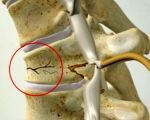

Компрессионный перелом возникает из-за чрезмерного сгибания спины, защитного напряжения паравертебральных мышц. Передние отделы позвоночника подвергаются давлению, превышающему конечную прочность кости. В результате участки кости прижимаются друг к другу, высота передней части позвонка уменьшается, он принимает форму клина. Место повреждения зависит от вектора приложения травмирующей силы. При падении на голову повреждаются шейные и верхнегрудные позвонки, поясничные позвонки, средние и нижние грудные позвонки на ногах, спине и ягодичной области.

Большинство компрессионных переломов у детей протекают без осложнений, то есть не сопровождаются неврологическими нарушениями. Осложненные поражения выявляются при сочетании компрессии с образованием отломков или взрывных переломов, при которых позвонок одновременно сжимается и разделяется на части в результате интенсивного травматического воздействия.